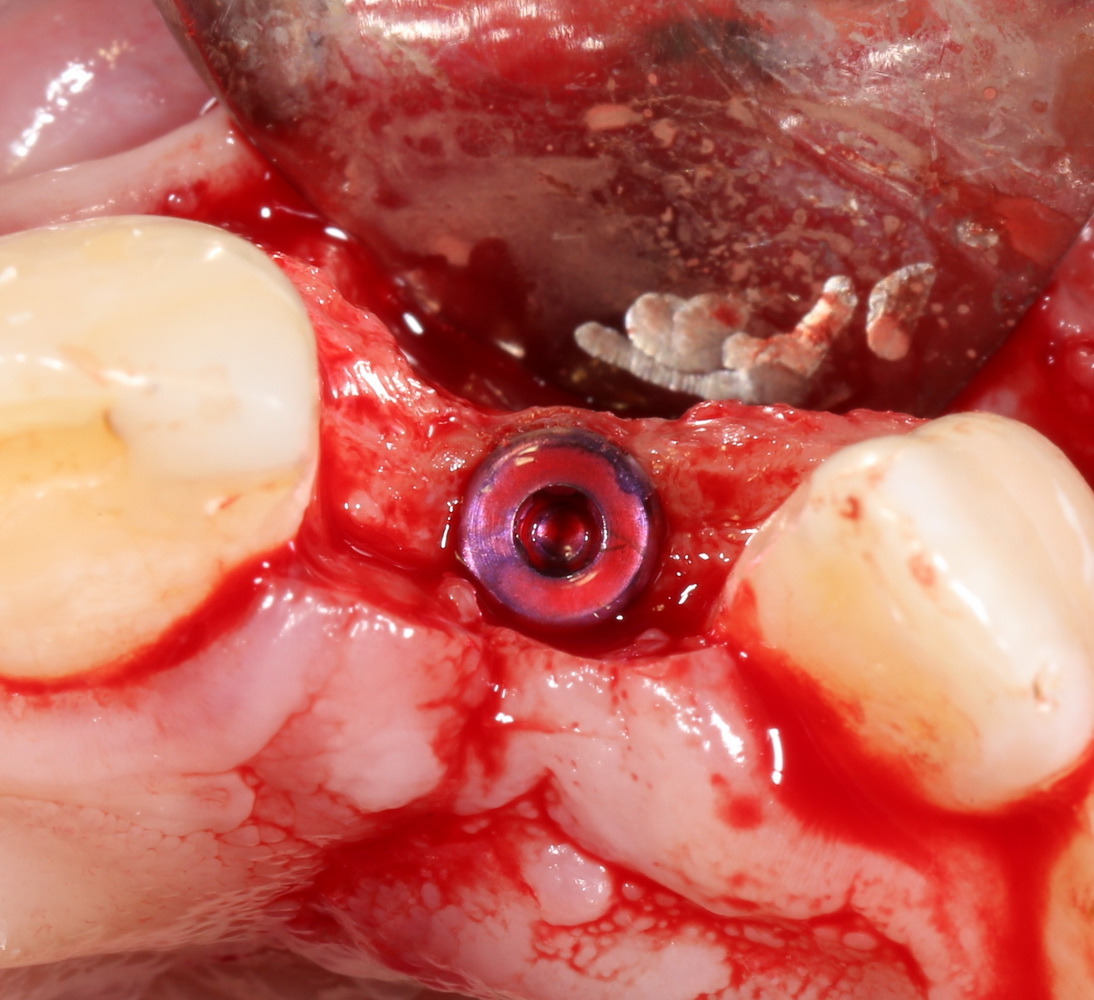

Например, в следующей ситуации:

Оставить так, как есть — это значит, сильно рисковать имплантом и объемом альвеолярного гребня — фактически, большая часть импланта пятого зуба «висит в воздухе». Поэтому получившуюся костную полость мы заполняем аутокостной стружкой в смеси с Bioss и закрываем коллагеновой мембраной BioGide: